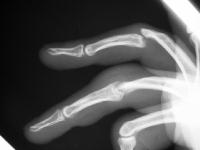

These are before and after radiographs of middle and ring proximal interphalangeal joints in a young man after a rotating blade injury resulting in dorsal bone and soft tissue loss. Initially treated elsewhere with K wire fixation, ring finger skin graft and abdominal flap reconstruction of the middle finger, he presented with instability, stiffness, pain and lateral angulation. Surgery was technically difficult because normal landmarks were distorted or missig. Despite complex bone and soft tissue loss,  stability was rendered in part by the restoration of concentric joint surfaces.

Lateral views:

Click for larger image